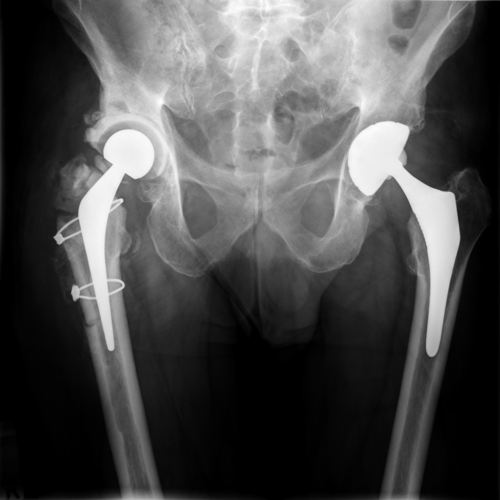

Pre-operative anteroposterior (AP) radiograph of the patient’s pelvis demonstrating bilateral hip replacements. On the right side there is significant bone loss of the proximal femur and greater trochanter. Osteolysis is also present around the uncemented acetabulum and its screws. There is eccentric wear of the polyethylene liner.